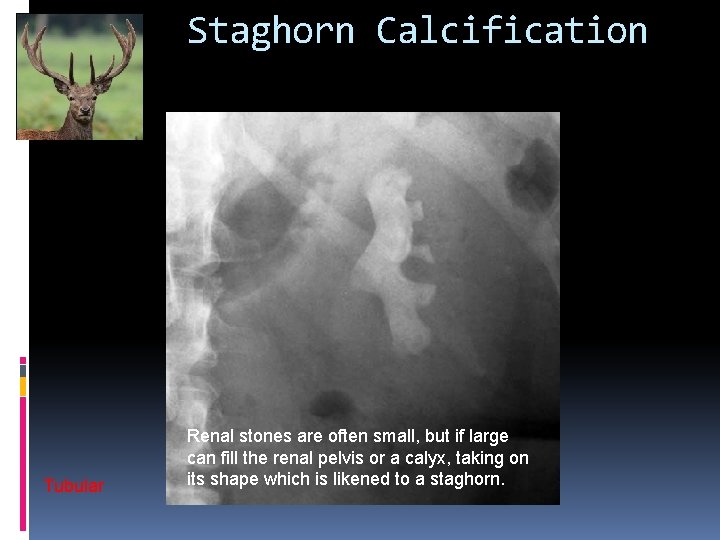

Staghorn Calcification Tubular Renal stones are often small, but if large can fill the renal pelvis or a calyx, taking on its shape which is likened to a staghorn.